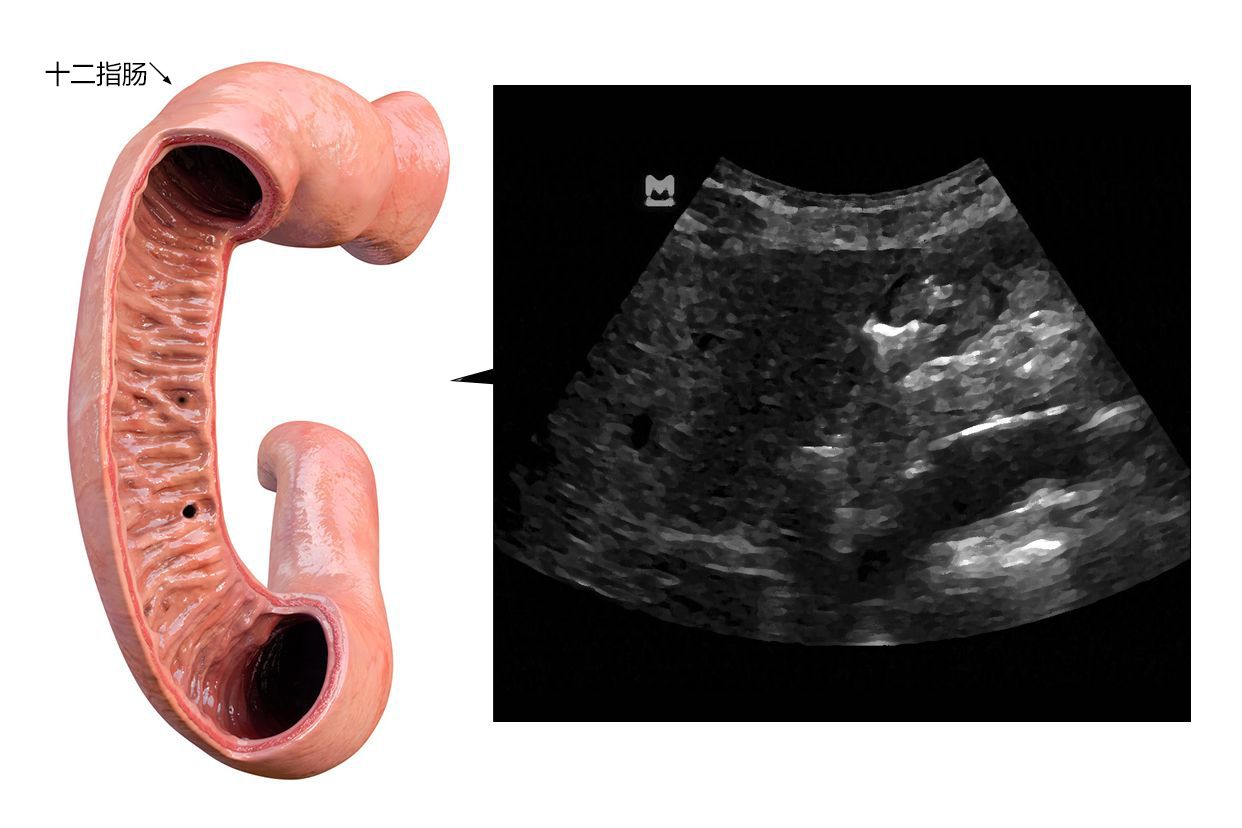

正常人体的十二指肠超声会显示胃部大小及轮廓正常,胃底壁光滑平整。

如果在进行十二指肠超声检查时发现黏膜组织缺损或造影机通过异常,表示自身可能存在疾病。

十二指肠超声主要是以造影检查为主,患者通过吞服造影剂的方式,由医生通过快速成片的方式来对患者的幽门、胃部轮廓、胃部褶皱黏膜进行观察,以明确患者是否存在十二指肠息肉、十二指肠梗阻等疾病。